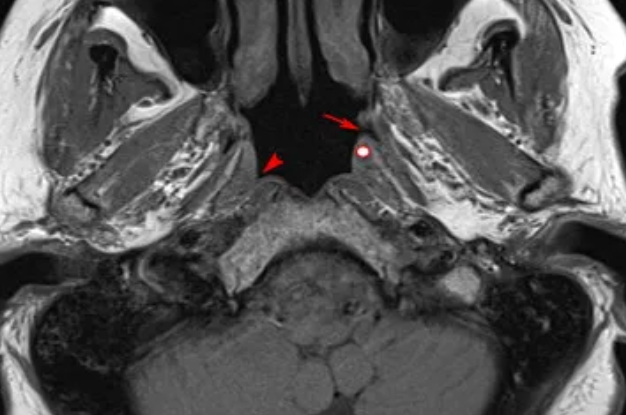

in my opinion, the final boss creeps at night down into the nasopharynx from the sinuses and from above the cribriform plate, in search of leftover piece of food; pieces of food get stuck in the complex folds of the nasopharynx (e.g. fossa of Rosenmuller), deep in the gums, and some people even develop a pouch called "Zenker's diverticulum" that can store a chunk of feed for the parasite to munch on at night-time;

caption: coincidentally, this is one of the regions where ENT (ear-nose-throat) specialists scrutinize for early signs of nasopharyngeal carcinoma (red arrowhead);

the skull base, facial bone, and the head-neck anatomy in general is very complex, with multiple orifices thru which an amorphous creature may move in search of feed; based on the sheer volume of stringy slime that i routinely expel thru the nose/mouth, i think that the organism moves throughout the central nervous system in pieces; in my opinion, one can even see them on MRI as "flow artifact;" the floaters in the eyes likely represent parasitic strings - u can best see then while looking up at the sky without sunglasses;